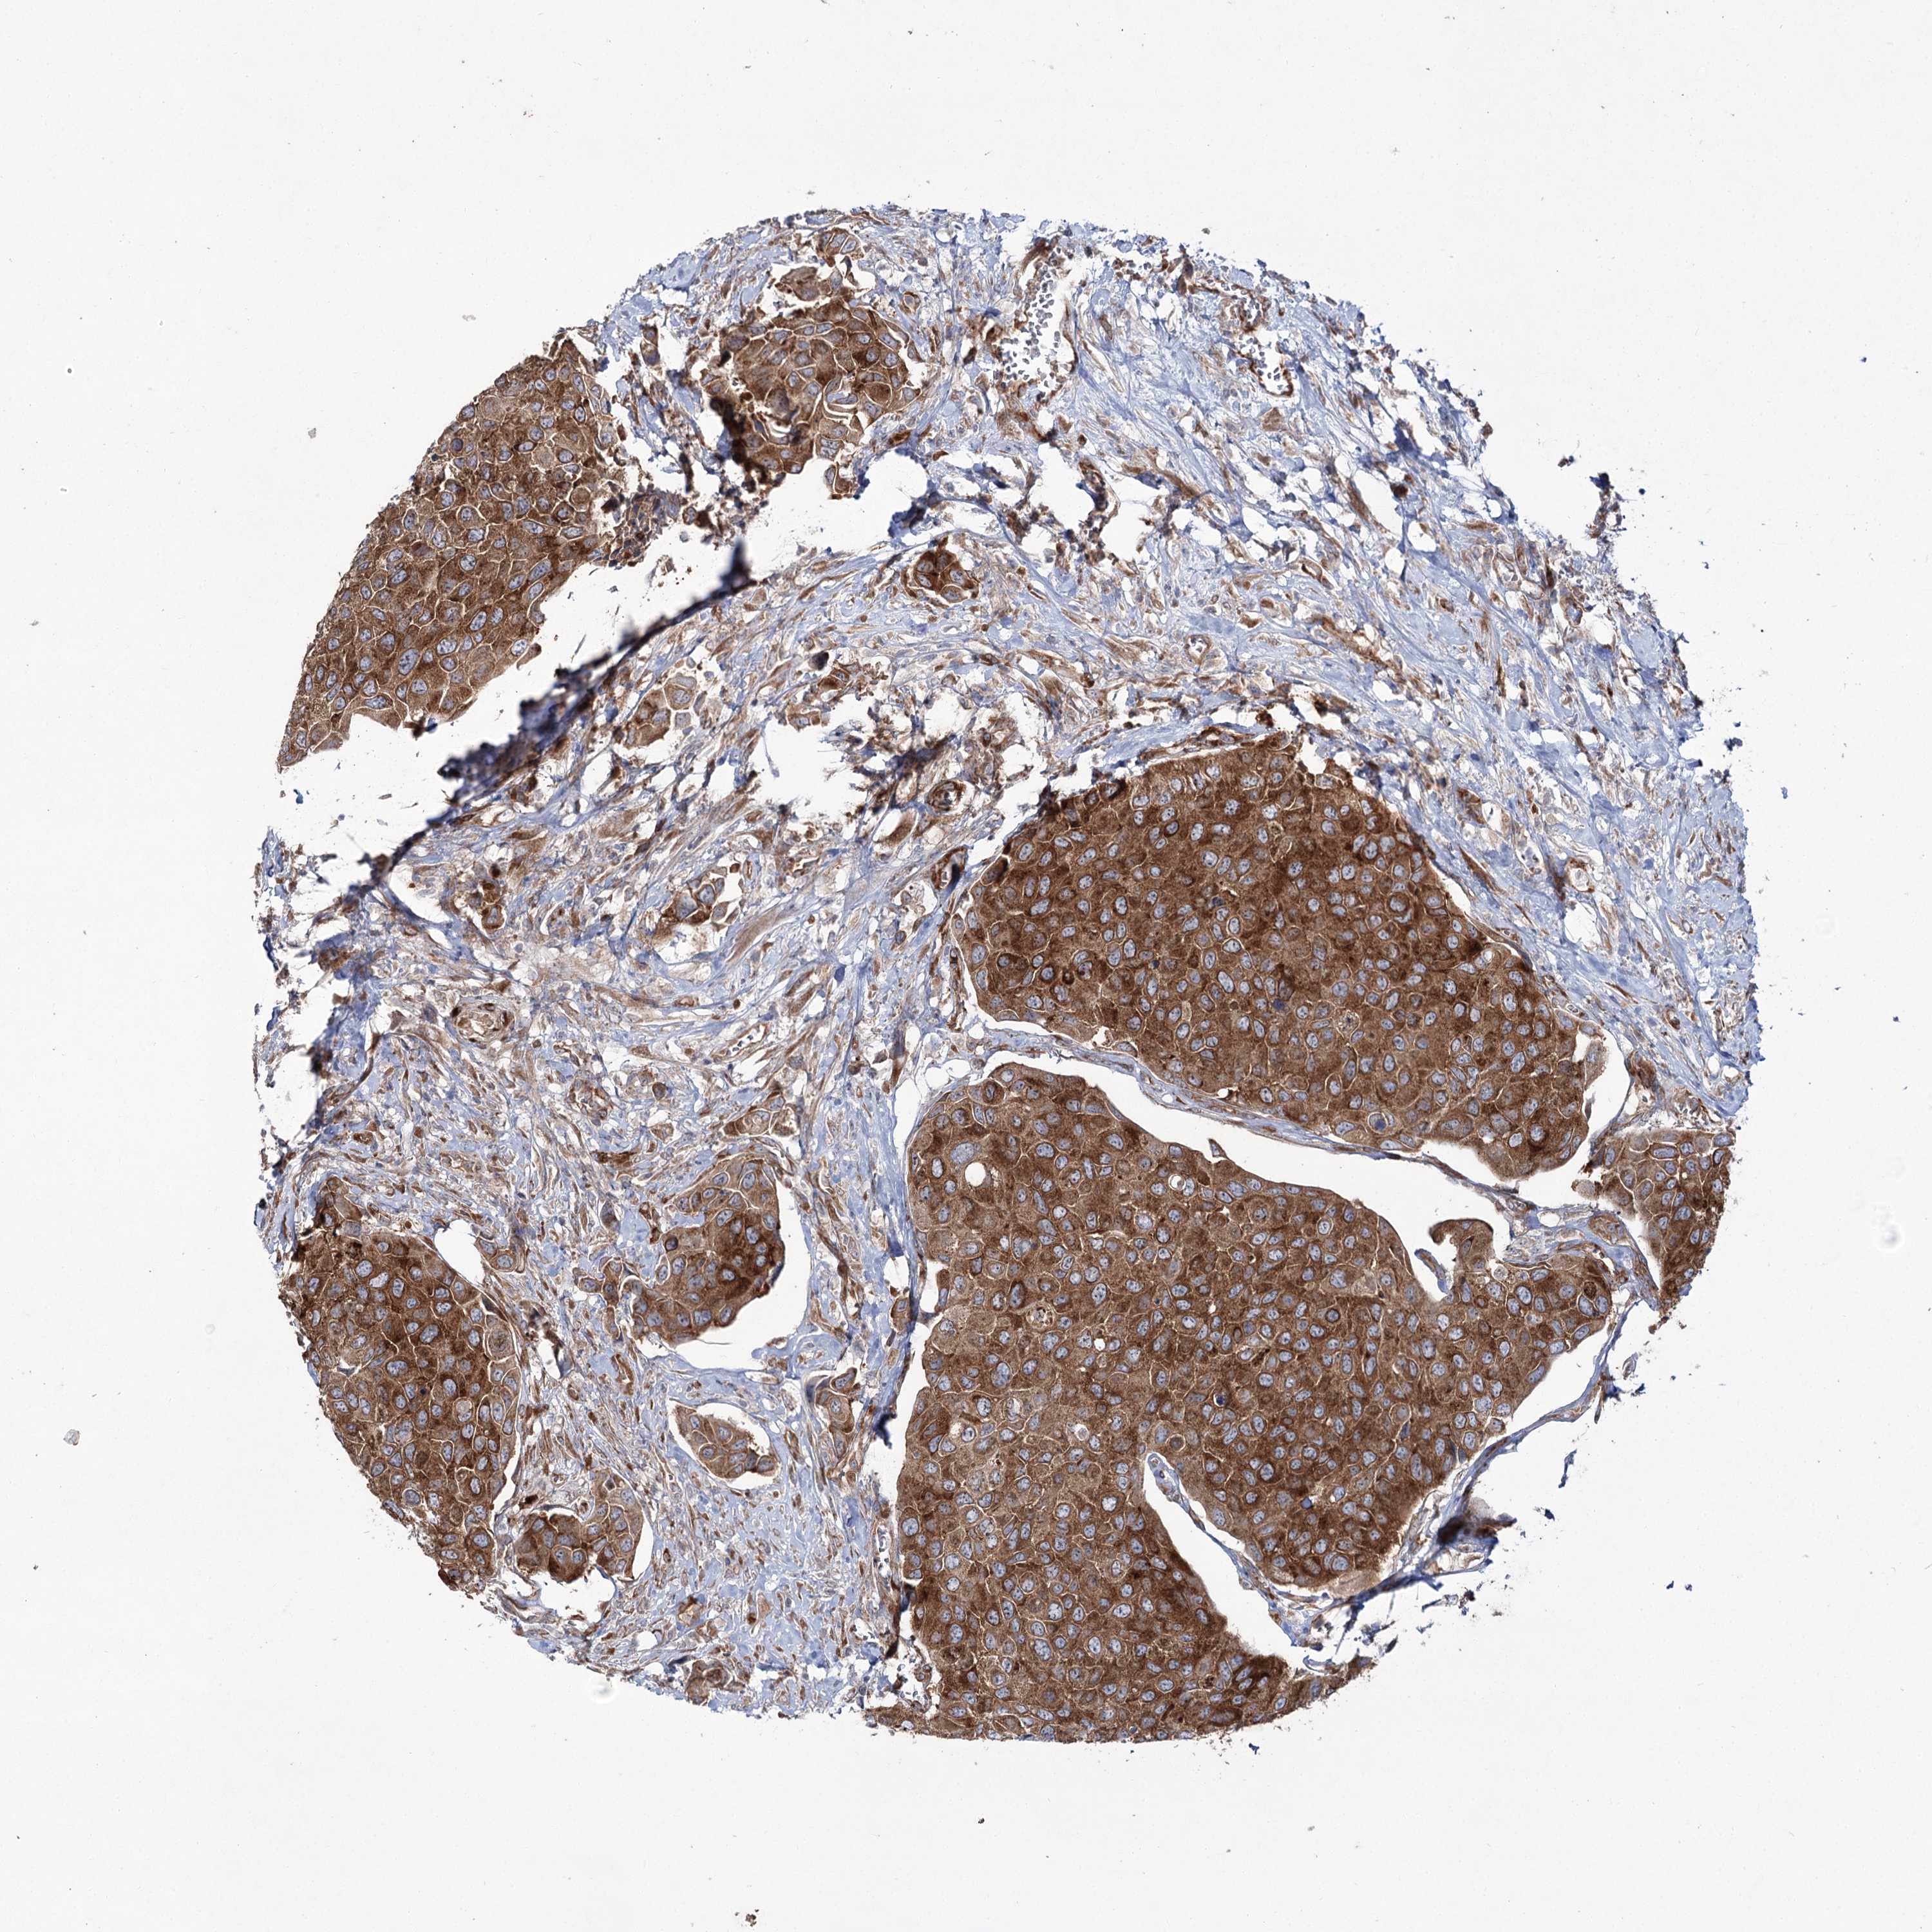

UROTHELIAL CANCER - Protein expressioni

A mouse-over function shows sample information and annotation data. Click on an image to view it in a full screen mode. Samples can be filtered based on level of antibody staining by selecting one or several of the following categories: high, medium, low and not detected. The assay and annotation is described here.

Note that samples used for immunohistochemistry by the Human Protein Atlas do not correspond to samples in the TCGA dataset.

Antibody stainingi

Antibody staining in the annotated cell types in the current human tissue is reported as not detected, low, medium, or high, based on conventional immunohistochemistry profiling in selected tissues. This score is based on the combination of the staining intensity and fraction of stained cells.

Each image is clickable and will lead to virtual microscopy that enables deeper exploration of all samples and also displays staining intensity scores, fraction scores and subcellular localization as well as patient and tissue information for each sample.

Antibody HPA037847

Staining

High

Medium

Low

Not detected

Intensity

Strong

Moderate

Weak

Negative

Quantity

>75%

75%-25%

<25%

None

Location

Nuclear

Cytoplasmic/membranous

Cytoplasmic/membranous,nuclear

Urothelial carcinoma, High grade

Urothelial carcinoma, Low grade

Urothelial carcinoma, NOS